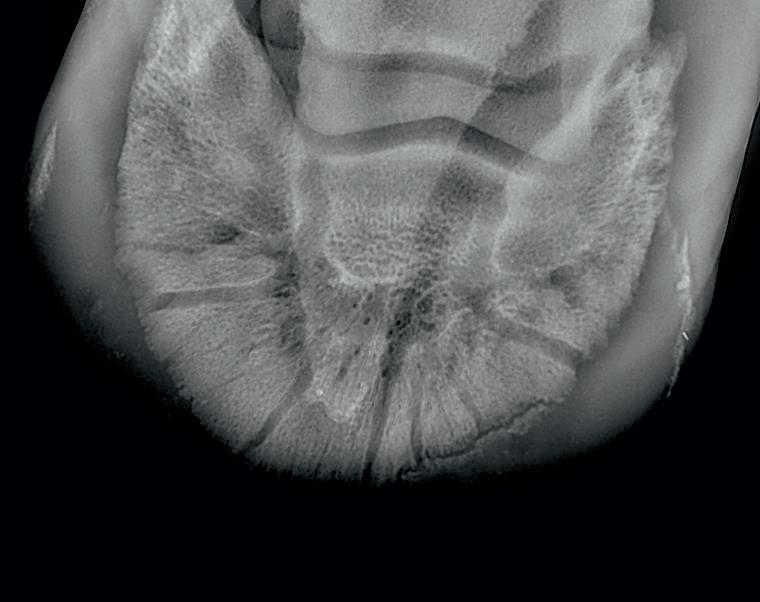

Radiographic proof in clinical results

BONE Gold nutritional bone joint and collagen supplement was formulated to provide some of the essential amino acid requirements of collagen type I, II and III (found in bone and connective tissue) in addition to supporting the nitric oxide pathway which has been found to assist in the formation of bone callus postinjury.

Here is a veterinary radiographic report on a horse with a fracture evident on the medial toe and after treatment and feeding Bone Gold during this period. More information on these products can be found at www.vetgold.com.au

VETERINARY RADIOGRAPHIC REPORT

HORSE: "XXXXXXXX"

DATES OF EXAMINATION: 26TH AUG, 21ST OCT 21 & 17TH NOV '21

HORSE: “XXXXXXXX”

PLACE: XXXXXXXXXX FARM

DATES OF EXAMINATION: 26TH AUG, 21ST OCT 21 & 17TH NOV ‘21

XXXXXXX's left and right front feet were radiographed on 26th Aug, 21st Oct (8 weeks) and again on the 17th Nov '21(12 weeks).

XXXXXXX’s left and right front feet were radiographed on 26th Aug, 21st Oct (8 weeks) and again on the 17th Nov ‘21(12 weeks).

RADIOGRAPHS:

26.08.21: Right Front: Large P3 solar margin fracture evident on medial toe 32.6mm x 4.1mm with approximately 1.4mm separation from parent bone as below left image.

21.10.21: Right Front: Fine residual 4.2mm fracture still evident, approximately 90% resolution

17.11.21: Right Front: Fracture fully resolved

26TH AUG 21

21ST OCT 21

Radiographic results as of the 17th Nov '21 show total resolution of the original fracture.

XXXXXXX was reshod today utilising off an alloy shoe with a toe clip - inner circumference seated out to avoid any sole pressure. The horse can return to training.

Please do not hesitate to contact me if you have any further queries

COMMENTS:

Solar margin Type IV fractures of this magnitude have well-documented internationally published healing rates of 7 - 12 months. Full resolution of these fractures is rare as most often the fracture fragments are resorbed. Full resolution in a 3 month period was not anticipated.

The horse was on Bone Gold 3 x scoops fed once per day for this period.

26th August 2021 21st October 2021 17th November 2021